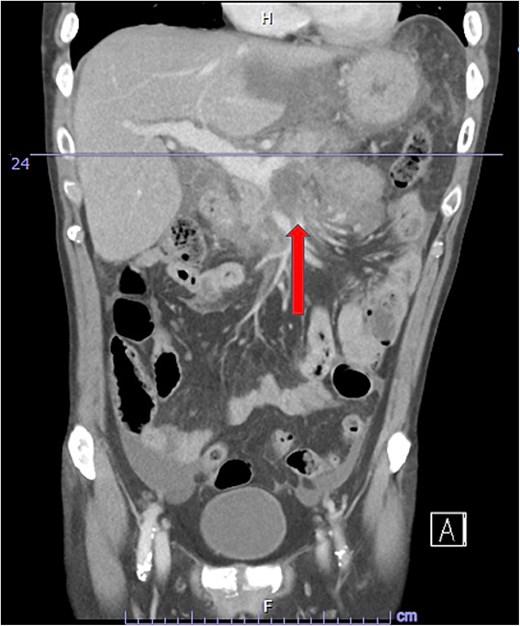

Despite the absence of abdominal symptoms, a computed tomography of the abdomen and pelvis (CTAP) was performed due to markedly elevated lipase levels. The CTAP (Figs 3–5) revealed evidence of acute pancreatitis (Fig. 5, arrow), with a complex peripancreatic fluid collection (Fig. 3, arrow). Additionally, a focal thrombus was observed within the portal venous confluence (Fig. 4, arrow). Further ultrasound of the gallbladder was negative for gallstones (Fig. 6), ruling out gallstone-induced pancreatitis.

CTAP coronal view; focal thrombus within the portal venous confluence (arrow).